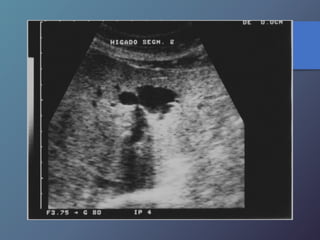

Enfermedad de Caroli

• Enfermedad autosómica recesiva.

• Dilatación sacular de árbol biliar intrahepático.

• Alta incidencia de litiasis y colan-gitis debido a

estasis biliar.

• US: imágenes quísticas que comuni-can con ramas

de árbol biliar. Cal-culos en la dilataciones saculares.

Enfermedad de Caroli •Enfermedad autosómica recesiva. • Dilatación sacular de árbol biliar intrahepático. • Alta incidencia de litiasis y colan-gitis debido a estasis biliar. • US: imágenes quísticas que comuni-can con ramas de árbol biliar. Cal-culos en la dilataciones saculares.